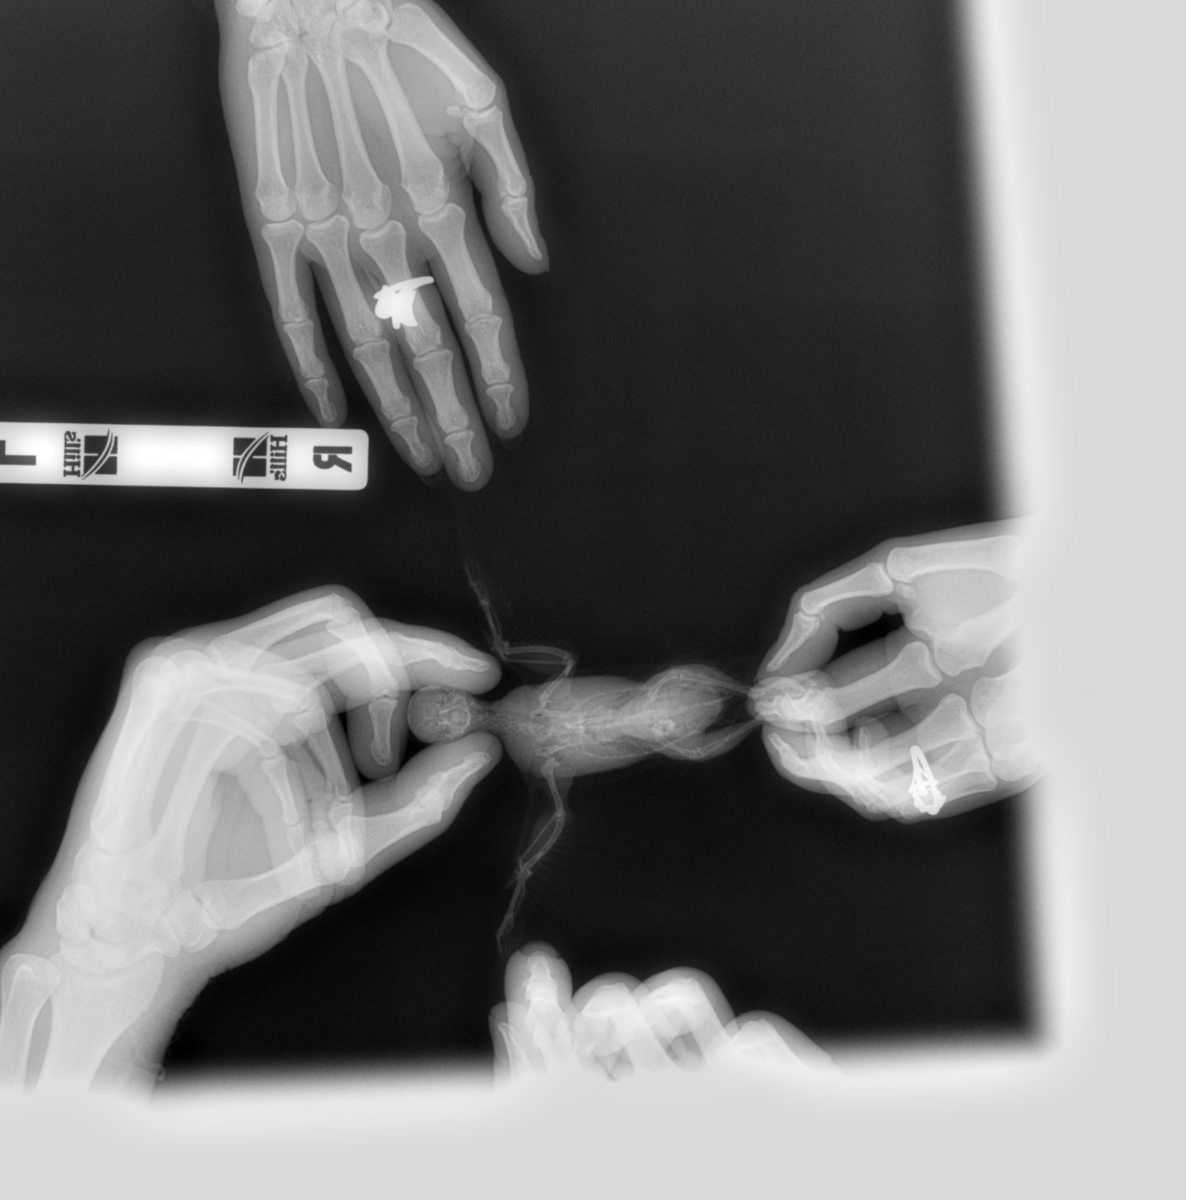

Venni Опубликовано 24 марта, 2019 Автор #117 Опубликовано 24 марта, 2019 (изменено) Всем здравствуйте. Сегодня были в вет.клиники. Врач брал мазок из зоба и клоаки- есть большое количество тонких, длинных палочек, но не мегабактерий, я ему даже фото с инете показывала мегабактерий под микроскопом, сказал не они, может и есть мегабактерии, но на фоне приёма противонрибковых лекарств, он их не видит, так же сделали рентген, рентген показал, что кишечник увеличен, печень в норме, полное описание скинет мне на почту вечером. По поводу бак.басева, у них только можно сделать на сальмонеллу, криптоспоридии и туберкулез, но этого мало, говорит вам в Воронеже нигде полный бак.пасев не сделает, делают только надо в Москву ехать, там лаборатории делают. Завтра буду звонить в обл.ветеринарную лабораторию, просить сделать бак.пасев., если нет, то хоть на эти 3 инфекции сдам, хотя толку мало. Как поддержать сейчас кишечник? Он ничего не назначил, говорит нужны анализы. Изменено 24 марта, 2019 пользователем Venni

KamaRo Опубликовано 24 марта, 2019 #118 Опубликовано 24 марта, 2019 @Venni выложите снимок рентгена, Зося его посмотрит и почитает. На счет мегабактерий и препаратов - болезнь неизлечимая, поэтому возбудитель может присутствовать в анализах. Как то удивительно, что обыватель ветеринару скидывает фото мегабактерий. Обычно вет.орнитологи, которые проводят и лабораторную диагностику, сами с атласами работают и консультируются у коллег более высокой квалификации. Нам вет.орнитолог даже группу возбудителей по микроскопии помета назвал, а посевом уже вид определяли и соответственно чувствительность к препарату. А как у собак/кошек возбудителей находят, ведь явно посевы делают? Областная вет.лаборатория как правило делает и бакпосев и микологический. На счет как поддержать кишечник, назначения уже дали - пробиотики, гепатопротекторы

Venni Опубликовано 25 марта, 2019 Автор #124 Опубликовано 25 марта, 2019 (изменено) Помёт на самом деле жёлто-зелёный, сейчас смотрю на фото очень светлый, хотя в телефоне цвет жёлто-зелёный. Выкладываю рентген. 9999_00014674.DCM 9999_00014673.DCM Изменено 25 марта, 2019 пользователем Venni

Venni Опубликовано 25 марта, 2019 Автор #125 Опубликовано 25 марта, 2019 (изменено) Сегодня сдали комлексный бак.посев с чувствительностью к антибиотикам, бактериофагам и антимикотическим препаратам. Пришлось вчера звонить в Москву в веттест, объяснила какой анализ мне нужен, сказали сделают, дали перечень вет.клиник в Воронеже с которыми они работают, где возьмут посев, правда долго делать будут 9-21 день, взависимости от роста. Изменено 25 марта, 2019 пользователем Venni

Venni Опубликовано 27 марта, 2019 Автор #134 Опубликовано 27 марта, 2019 @Zosia @Zosia Здравствуйте. Посмотрите пожалуйста наш рентген. На сколько пострадали органы от мегабактерий. 9999_00014673.DCM 9999_00014674.DCM

Venni Опубликовано 28 марта, 2019 Автор #135 Опубликовано 28 марта, 2019 @Zosia Добрый день. Посмотрите пожалуйста наш рентген. Файлы еле открыла. Извините, не разбираюсь в технике совсем.